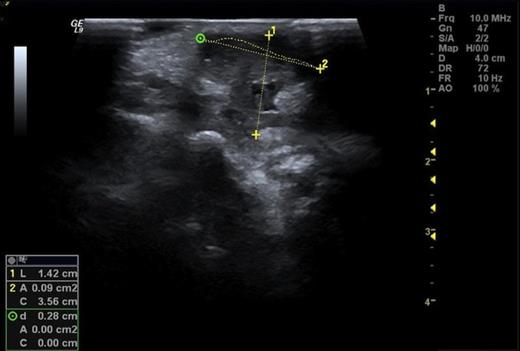

She presented again at the orthopaedic clinic 26 months later with continuing swelling and pain. Ultrasound showed a synovial tumour on the dorso-medial aspect of the wrist (Figure 1). Aspiration of the cyst produced a small amount of pus. She was admitted for incision and drainage of the abscess. Microscopy of the tissue showed a granulomatous inflammation.

Ultrasound showing a synovial tumour on the dorsal medial aspect of the wrist